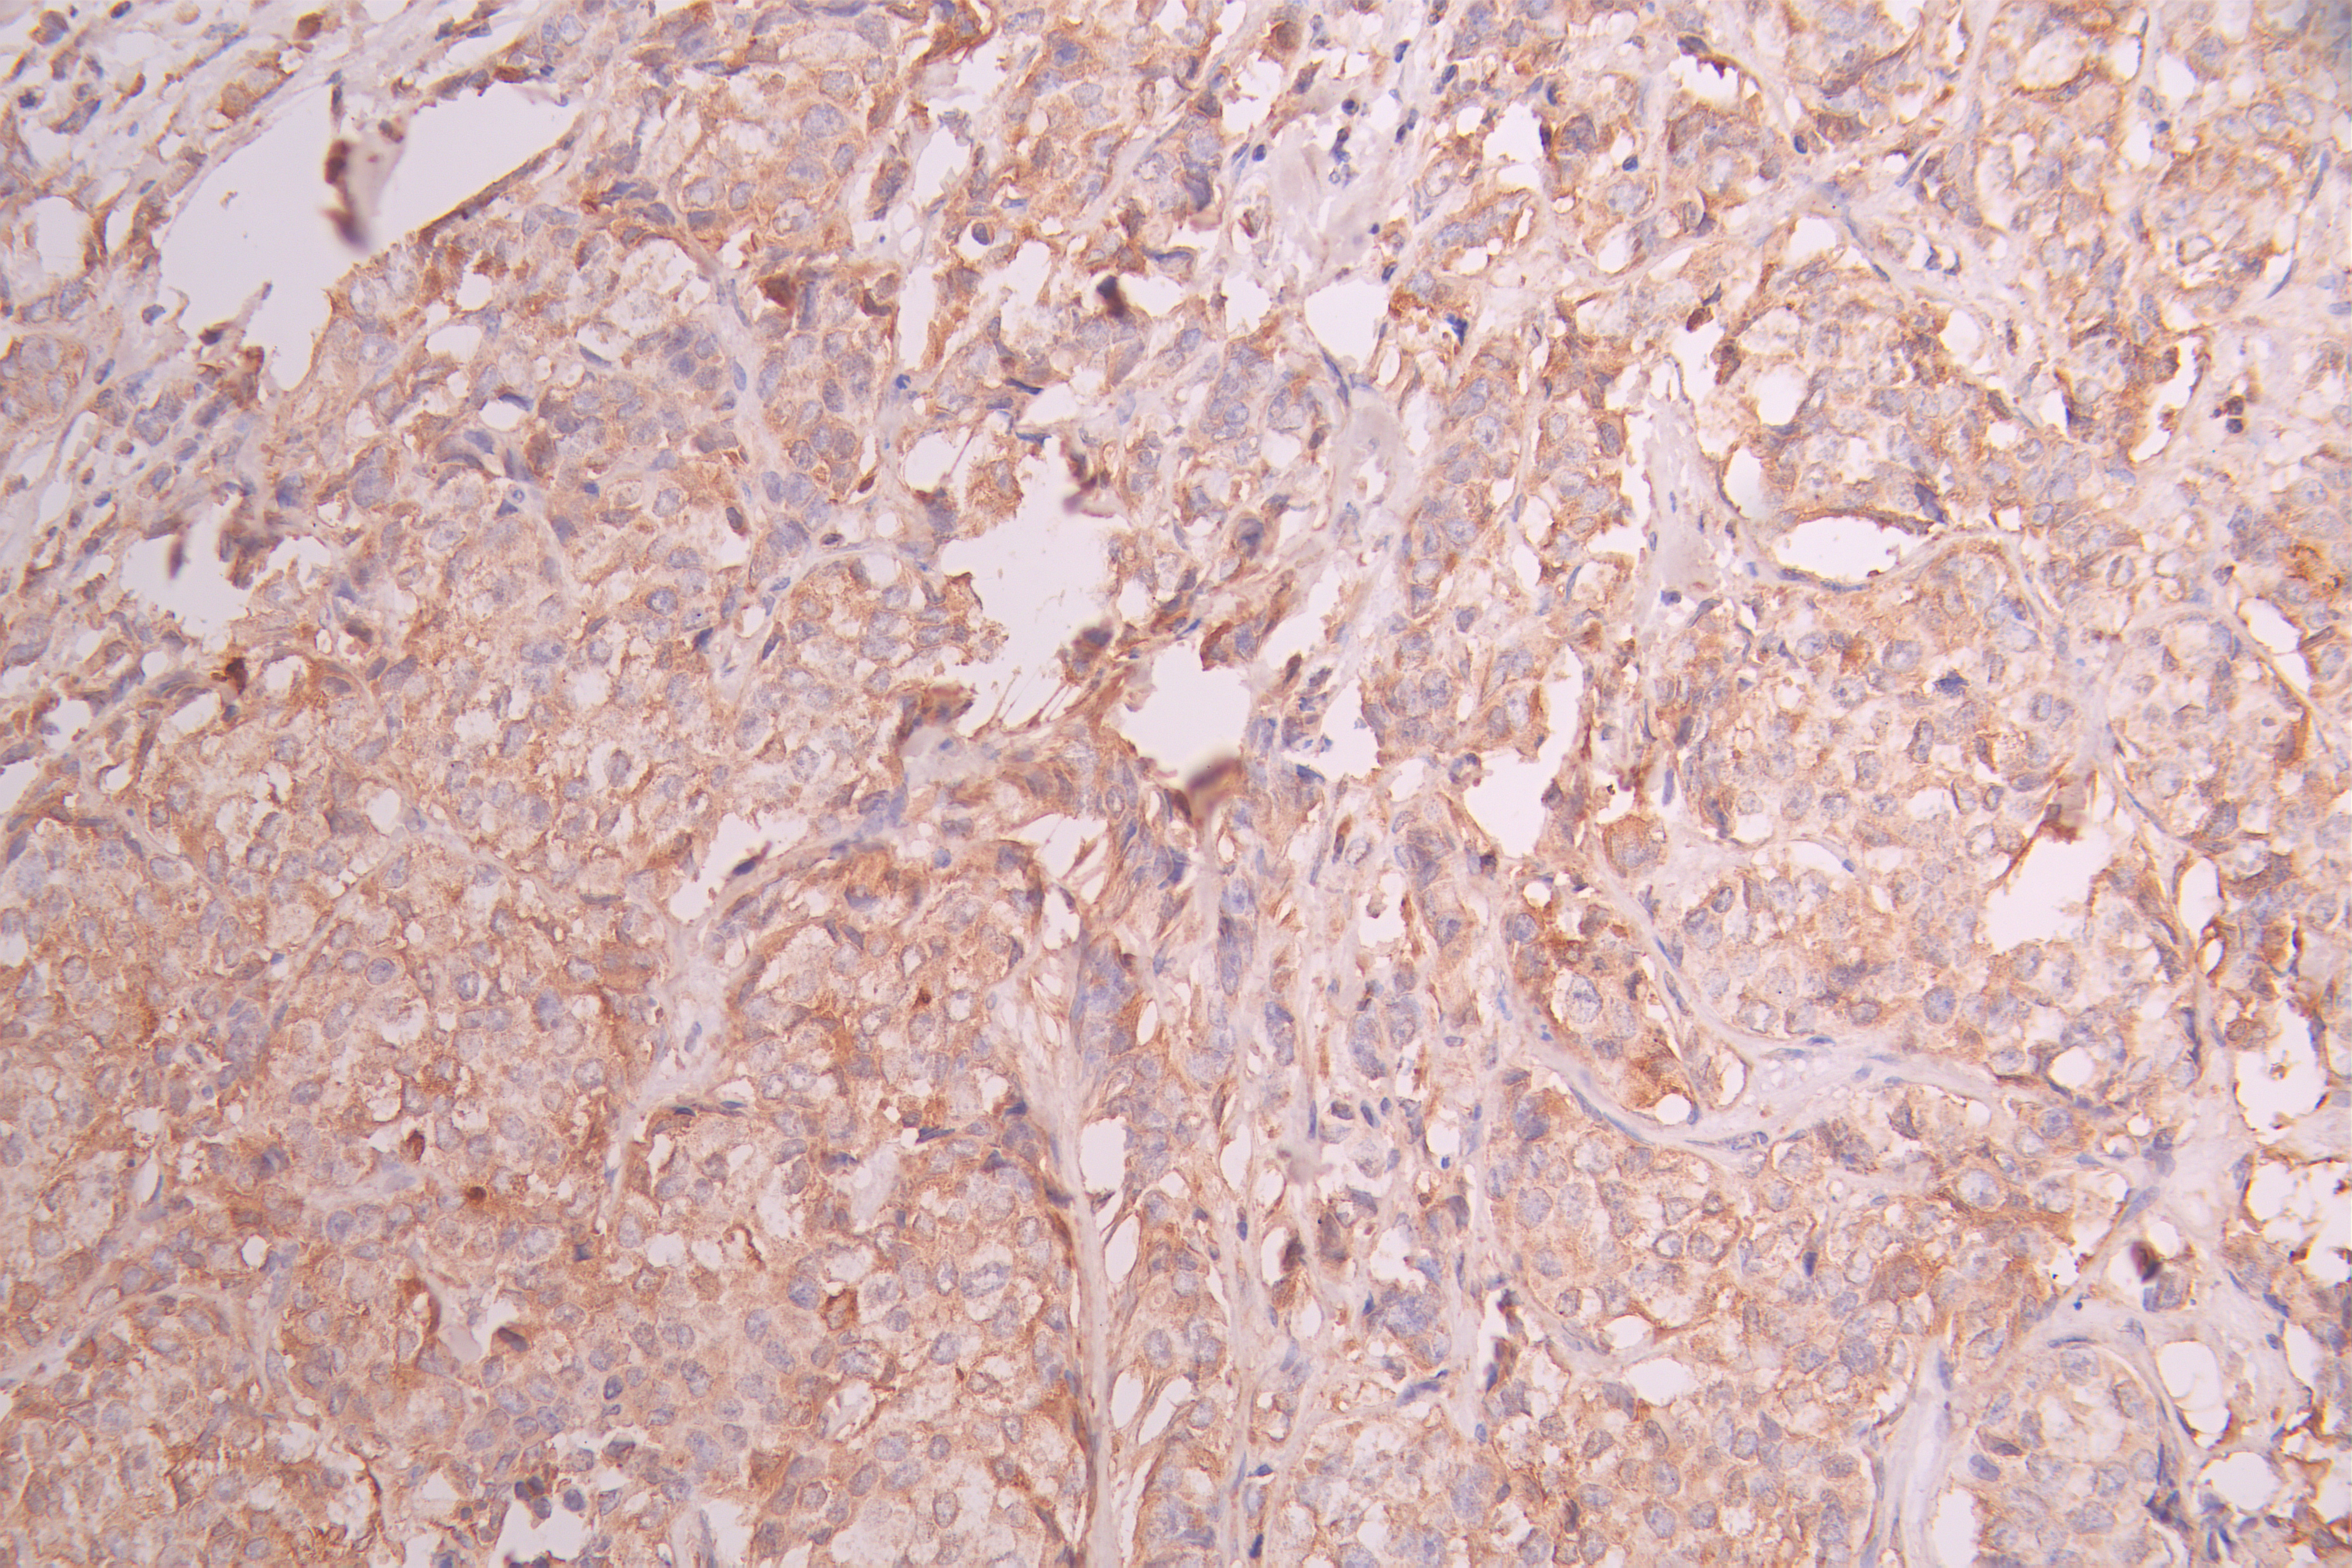

IHC image of CSB-RA215300A0HU diluted at 1:100 and staining in paraffin-embedded human breast cancer performed on a Leica BondTM system. After dewaxing and hydration, antigen retrieval was mediated by high pressure in a citrate buffer (pH 6.0). Section was blocked with 10% normal goat serum 30min at RT. Then primary antibody (1% BSA) was incubated at 4°C overnight. The primary is detected by a Goat anti-rabbit polymer IgG labeled by HRP and visualized using 0.05% DAB.